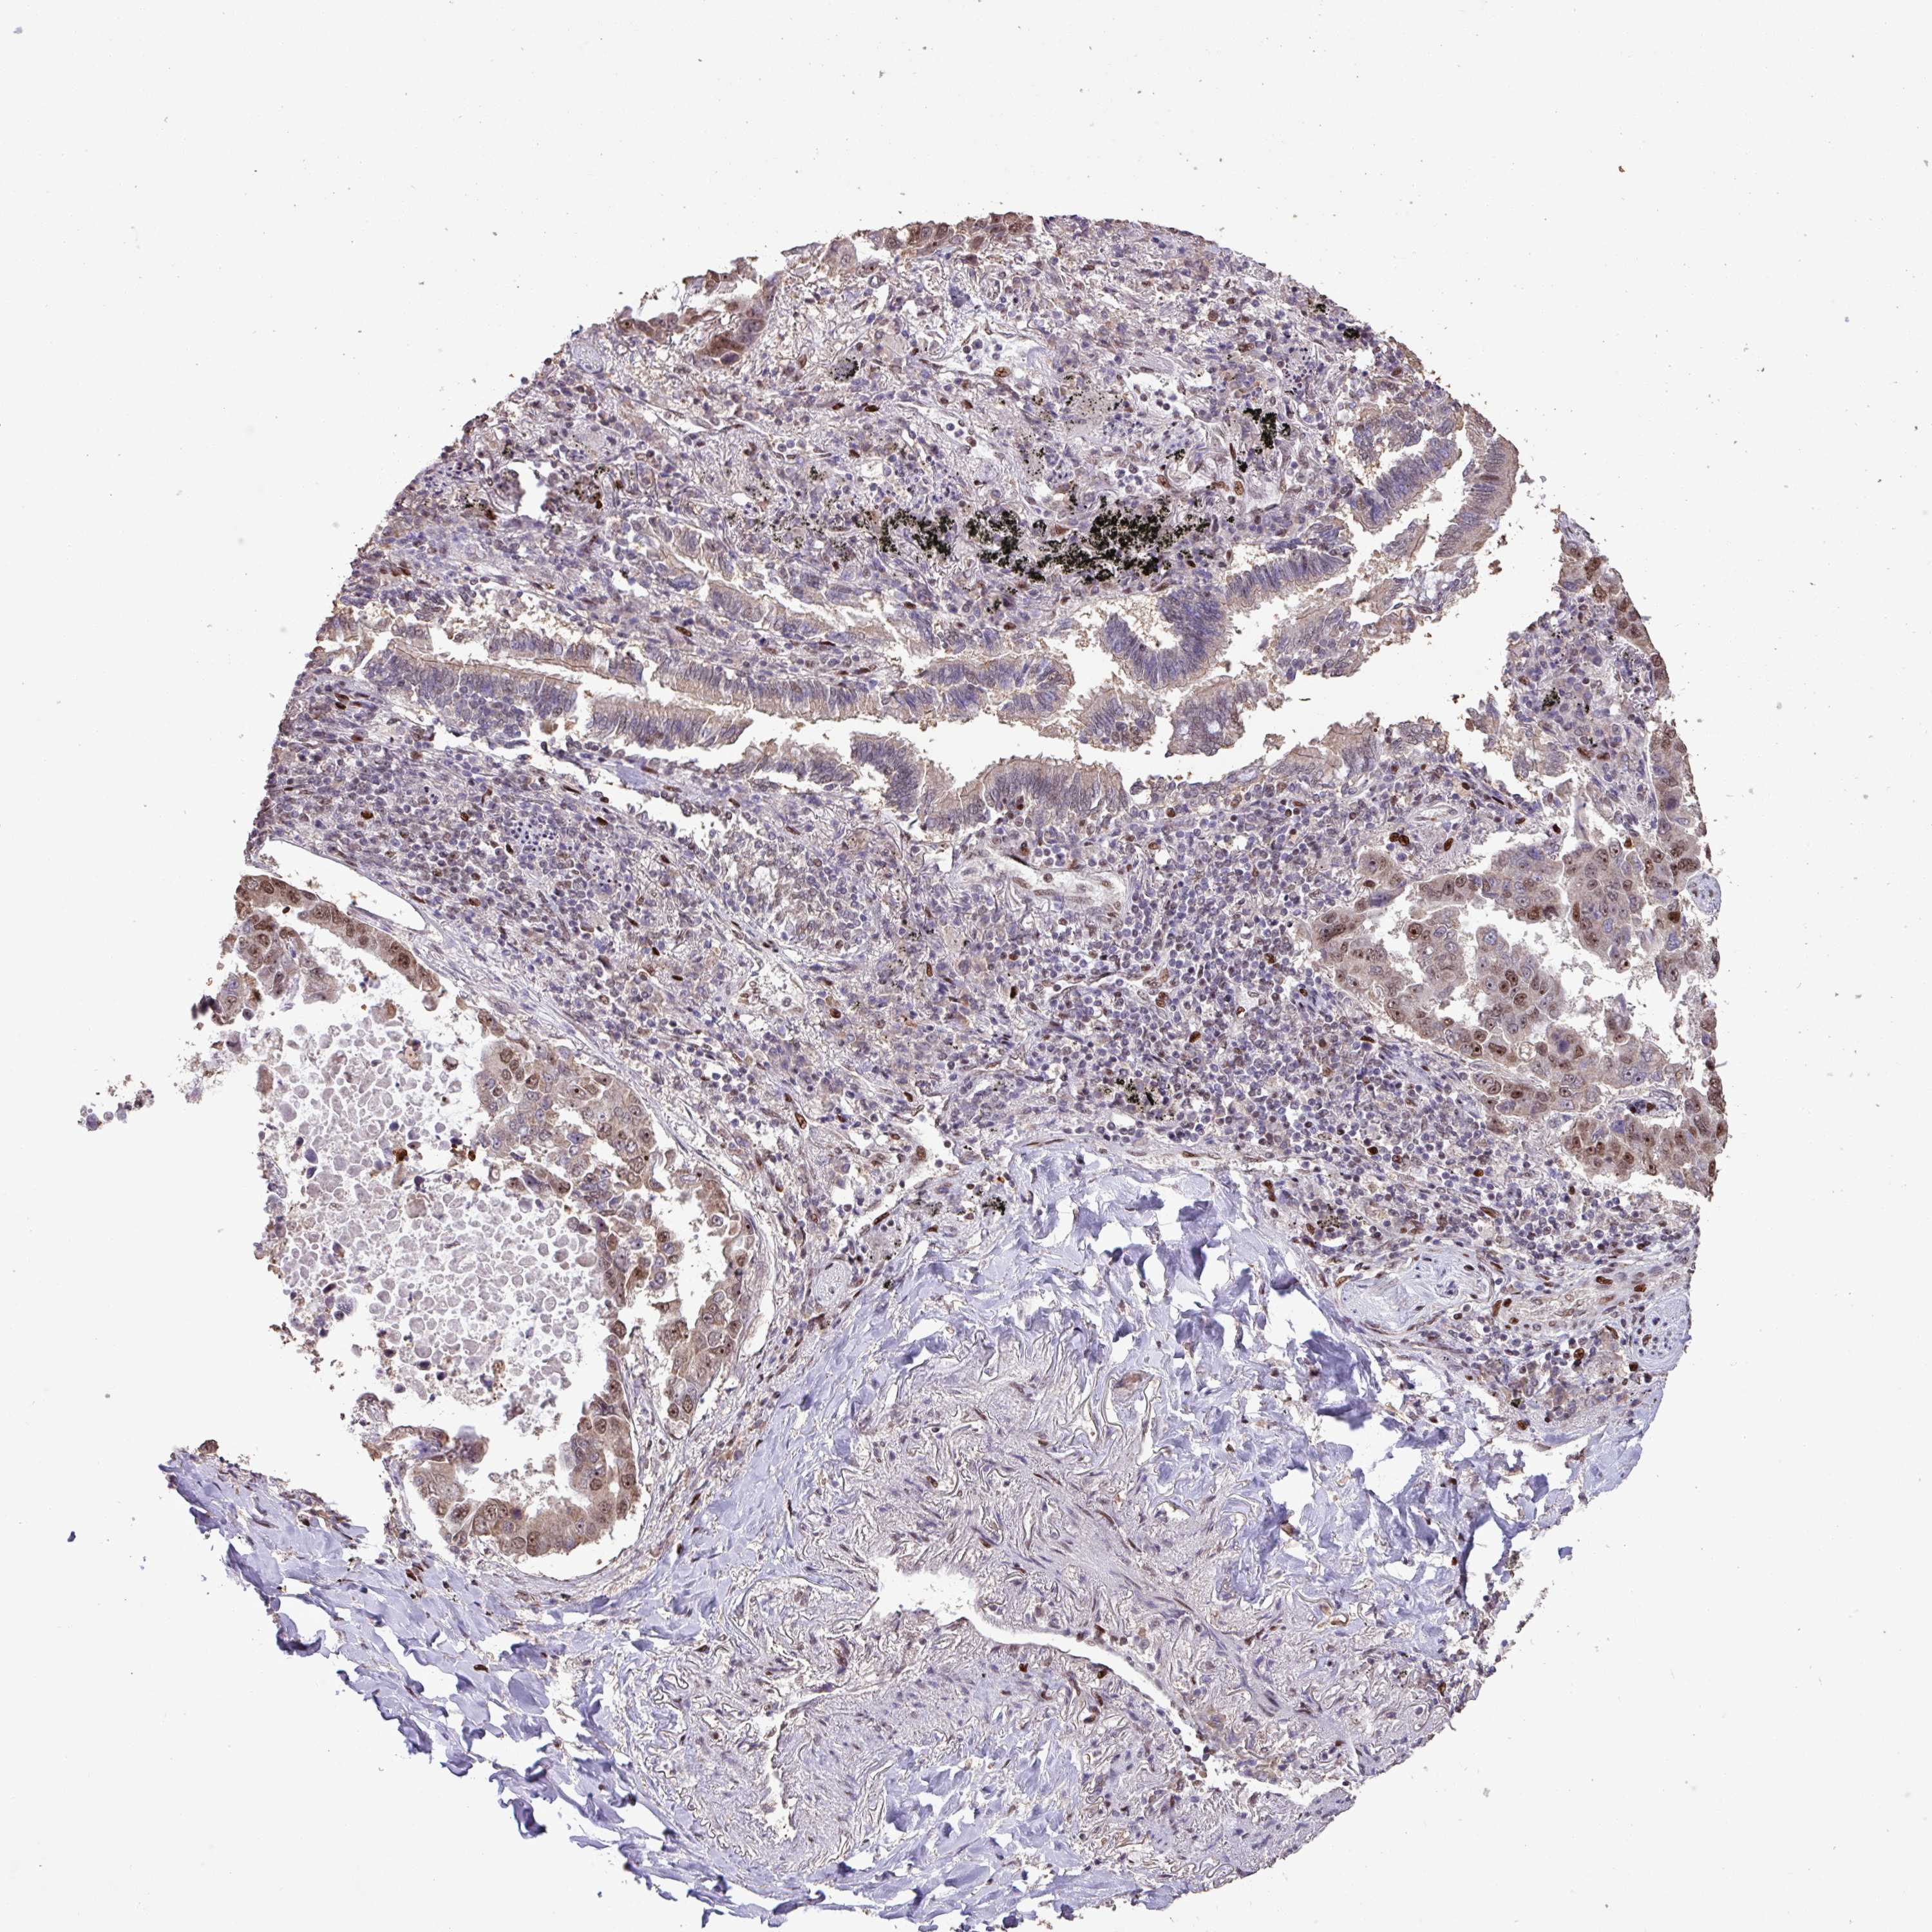

LUNG SQUAMOUS CELL CARCINOMA (TCGA) - Interactive survival scatter ploti

The Survival Scatter plot shows the clinical status (i.e. dead or alive) for all individuals in the patient cohort, based on the same data that underlies the corresponding Kaplan-Meier plots. Patients that are alive at last time for follow-up are shown in blue and patients who have died during the study are shown in red.

The x-axis shows the expression levels (FPKM) of the investigated gene in the tumor tissue at the time of diagnosis. The y-axis shows the follow-up time after diagnosis (years). Both axes are complimented with kernel density curves demonstrating the data density over the axes. The top density plot shows the expression levels (FPKM) distribution among dead (red) and alive patients (blue). The right density plot shows the data density of the survived years of dead patients with high and low expression levels respectively, stratified using the cutoff indicated by the vertical dashed line through the Survival Scatter plot. This cutoff is automatically defined based on the FPKM cutoff that minimizes the p-score. The cutoff can be changed by dragging the vertical line or by entering a cutoff value in the square labeled "Current cut-off".

Under the Survival Scatter plot the p-score landscape (black curve; left axis) is shown together with dead median separation (red curve; right axis). Dead median separation is the difference in median mRNA expression between patients who have died with high and low expression, respectively. It is calculated as follows: median FPKM expression of dead patients with high expression - median FPKM expression of dead patients with low expression. This is intended to aid the user in visually exploring custom cutoffs and the associated p-scores and dead median separation.

Individual patient data is displayed and can be filtered by clicking on one or more of the category buttons on the top of the page. Categories describing expression level and patient information include: high, low, alive, dead, female, male and tumor stages. The scale of the x-axis can be toggled between linear and log-scale by clicking on the "x log" button. Mouse-over function shows TCGA ID, patient information and mRNA expression (FPKM) for each patient.

& Survival analysisi

Kaplan-Meier plots summarize results from analysis of correlation between mRNA expression level and patient survival. Patients were divided based on level of expression into one of the two groups "low" (under cut off) or "high" (over cut off). X-axis shows time for survival (years) and y-axis shows the probability of survival, where 1.0 corresponds to 100 percent.

ZNF709 is not prognostic in Lung Squamous Cell Carcinoma (TCGA)

Best expression cut offi

Based on the FPKM value of each gene, patients were classified into two groups and association between prognosis (survival) and gene expression (FPKM) was examined. The best expression cut-off refers the FPKM value that yields maximal difference with regard to survival between the two groups at the lowest log-rank P-value. Best expression cut-off was selected based on survival analysis .

: N/A

P scorei

Log-rank P value for Kaplan-Meier plot showing results from analysis of correlation between mRNA expression level and patient survival.

N/A

5-year survival highi

5-year survival for patients with higher expression than the expression cutoff.

5-year survival lowi

5-year survival for patients with lower expression than the expression cutoff.

TCGA RNA samplesi

RNA-seq data is reported as average FPKM (number Fragments Per Kilobase of exon per Million reads), generated by the The Cancer Genome Atlas (TCGA) .

Normal distribution across the dataset is visualized with box plots, shown as median and 25th and 75th percentiles. Points are displayed as outliers if they are above or below 1.5 times the interquartile range. FPKM values of the individual samples are presented next to the box plot.

Average pTPM 0.7

Number of samples 489